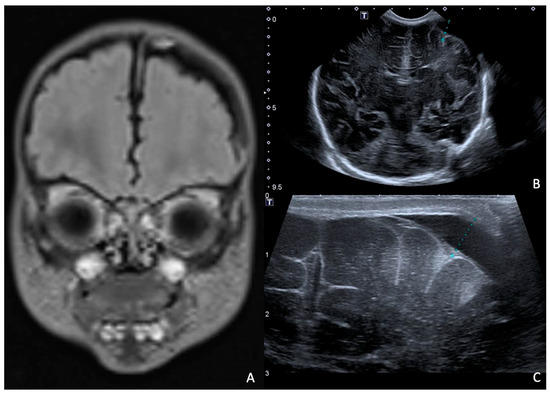

At 7 days of life, an HUS and a brain MRI were performed, showing a cerebral abscess lesion in the right caudate nucleus (Figure 8). Biochemical parameters in the CSF were normal. Blood and CSF cultures as well as PCR for neurotropic viruses and bacteria were negative. Empirical antibiotic therapy was modified by discontinuing ampicillin/sulbactam and starting broad-spectrum therapy with ampicillin, cefotaxime, and metronidazole.

Figure 8. HUS (A) and brain MRI in T2 sequence (B): abscess of approximately 1 cm in diameter (delimited by the letters A and B in (A)) at level of right caudate nucleus in context compatible with hypoxic–ischemic encephalopathy. MRI in T2 sequence showed evidence of rim and hyperintense core.